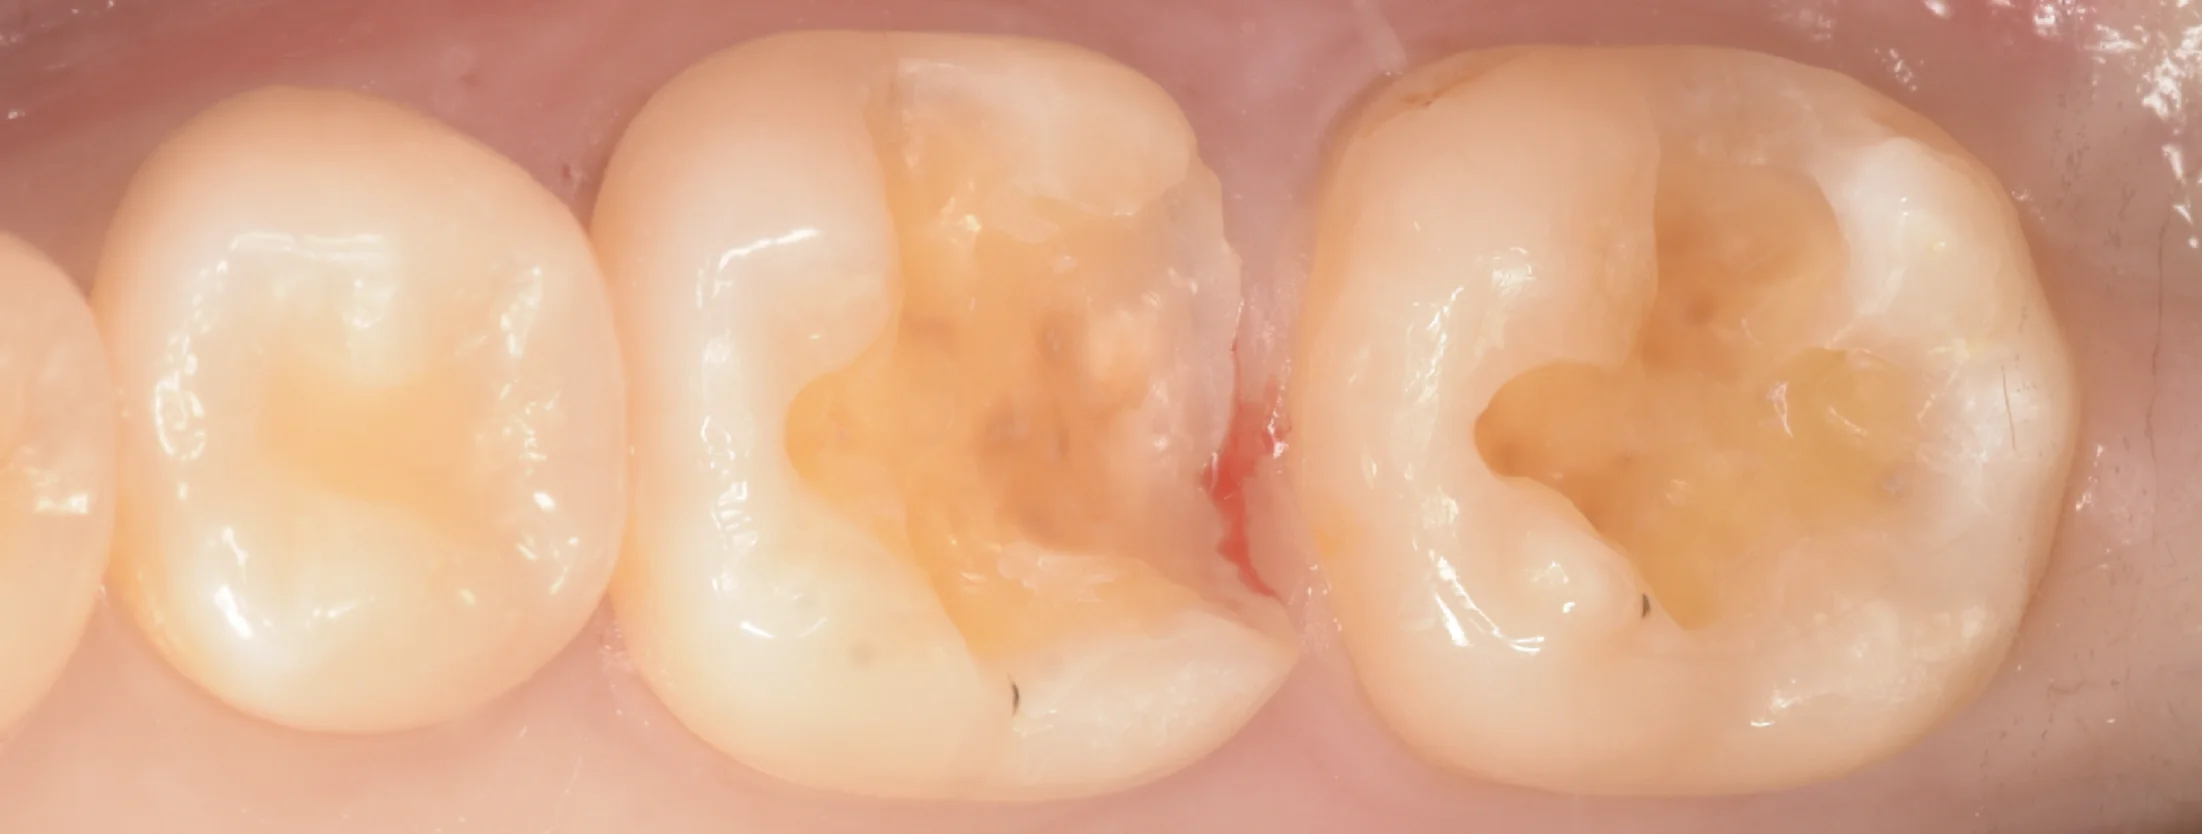

そして咬合調整・研磨が終わった最終的な状況がこちらです。

形態修正・研磨後

硬化後に重合収縮の影響か隣の歯とのあたりが弱くなってしまいました。

こうなると食べかすが挟まったりすることでまた歯肉に炎症が起こってしまいます。

すでに隣の歯との間を詰めてから5分以上経過してしまっているため、このまま処置しようとしてもくっつきません。

なので、表層を一層だけ削って、再度処理からやり直し歯の間のみをうっすら一層埋めました。

これで適切な当たりを再現できたので、終了です。

術前術後の写真がこちらです。

術前術後

遠方から長時間の治療、お疲れ様でした!

なるべく長く使えるといいですね!